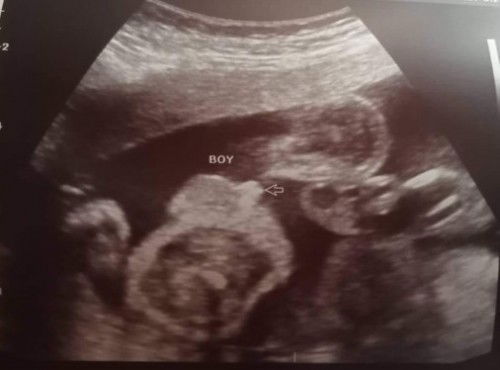

Posterior Low lying hanggang 5months bed rest malala may subchorionic hemorrhage din. Then ngayong 6months nag high lying na si placenta ☺️ and finally baby boy nagpakita na rin ng gender si baby 😅 shy type kasi nakaraan nakadapa daw ayaw bumukaka. Sa mga momsh na tulad ko low lying tyaga lang talaga sa bed rest & wag magpatagtag take your vitamins/meds and always consult sa OB . #1stimemom #pregnancy #BabyBoy #FTM #team_November